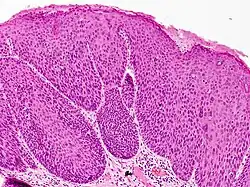

Bowenoid papulosis -

Bowenoid papulosis